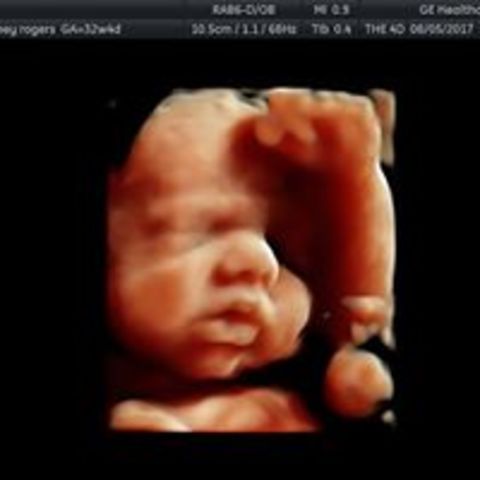

• Primera Tecnología en 3D

Primera Tecnología en 3D

Kazunori Baba de la Universidad de Tokio desarrolló la tecnología de ultrasonido por primera vez en 3D capturando imágenes tridimensionales de un feto.

• Desarollo de la tecnología en 4D a tiempo real

Desarollo de la tecnología en 4D a tiempo real

Ultrasonido 4-D (tiempo real) fue desarrollada por Thomas Nelson y su equipo de investigación. Esta tecnología permite crear una imagen de mayor calidad y precisión.